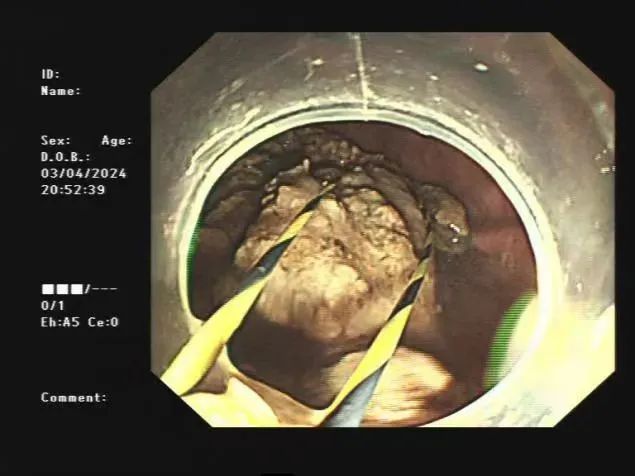

检查发现,她体内有一鹅蛋般大小黑褐色异物,异物钳探查异物较硬,并多发胃溃疡形成,结合病史,考虑胃巨大结石。

由于王奶奶胃内结石较大较硬,消化内科二病区医疗团队迅速为其设计个性化治疗方案,进行“内镜下胃石碎石取石术”。医生使用套圈器、斑马导丝反复碎石,通过取石网篮,将胃石分次取出。经过不懈努力,最终成功清除困扰患者的胃内鹅蛋般大小的结石,使王奶奶避免开腹手术的痛苦。